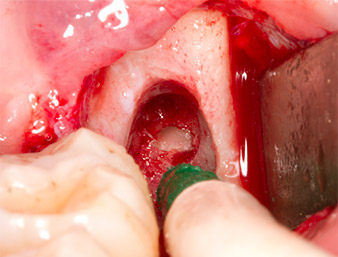

Sous bloc nerveux et anesthésie locale, le site d’intervention est ouvert et les tissus mous sont exposés afin d’accéder à la zone rétromolaire buccale (Fig. 3).

Incision du sulcus

Fig. 3 : L’incision du sulcus démarre au milieu de la dent 36 (LL6), avec extension distale sur le ramus ascendant.

Le tissu recouvrant le reste radiculaire n’est pas entièrement ossifié et est essentiellement constitué de tissu de granulation modifié par l'inflammation (Fig. 4).

Tissu de granulation

Fig. 4 : Deux écarteurs Lagenbeck et un raspatoire exposent la zone d’intervention. On aperçoit le tissu de granulation de la première ostéotomie non totalement cicatrisée.